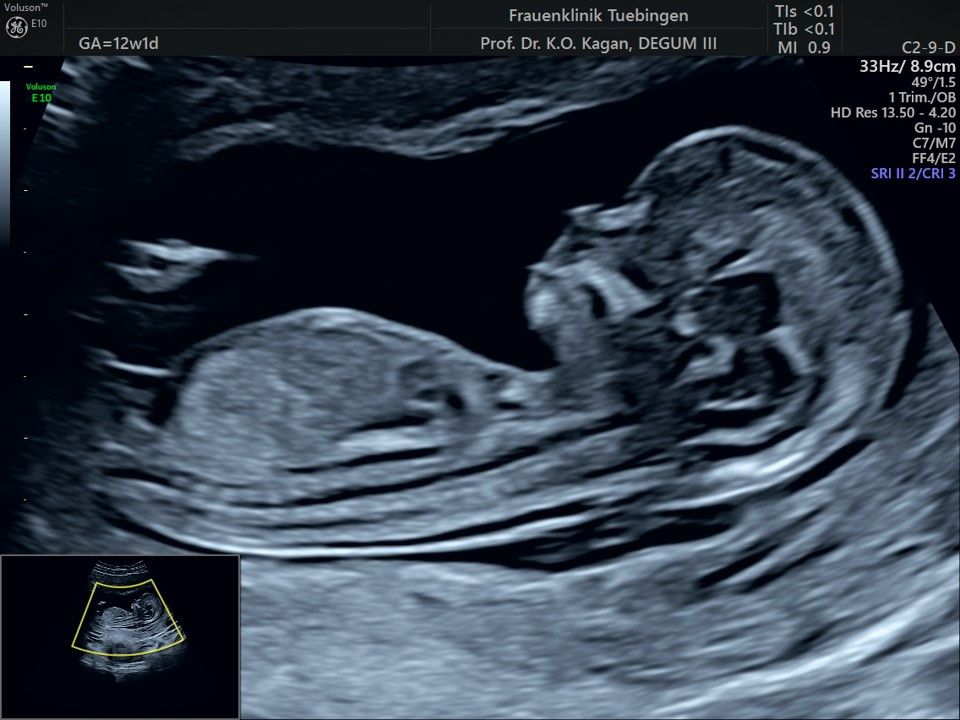

Das Ergebnis der Ultraschalluntersuchung ist wegweisend. Dabei wird der Fet vermessen, die Organe werden untersucht und die sonographischen Marker zur Risikoberechnung für Chromosomenstörungen werden beurteilt. Das sind: die Nackentransparenzdicke, Nasenbein sowie der Blutfluss in der rechten Herzhälfte und im Ductus venosus, einem Gefäß in der Leber des Feten.

Findet sich eine Fehlbildung oder ist die Nackentransparenzdicke deutlich erhöht, werden wir mit Ihnen eine Abklärung mittels Fruchtwasser- oder Mutterkuchenpunktion besprechen. Ob diese dann tatsächlich durchgeführt wird, müssen wir in einem gemeinsamen Gespräch klären.